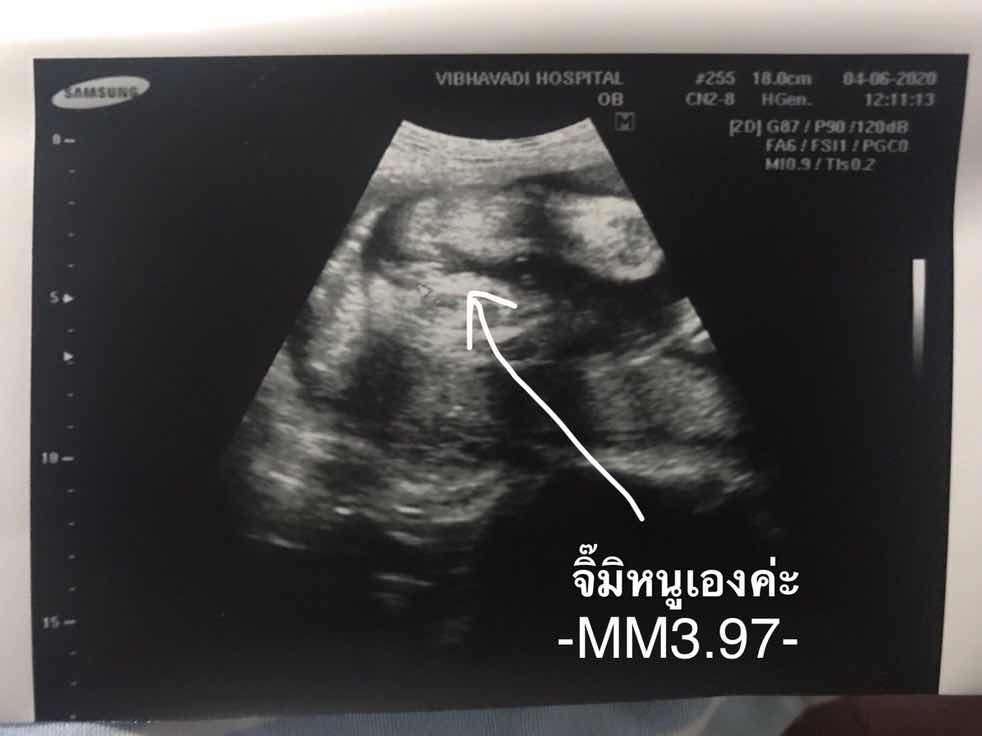

นี้จิมิใช้มั่ยค่ะ ไม่น่าจะเปนไข่เนาะ😂

ชัดแจ๋วค่ะ